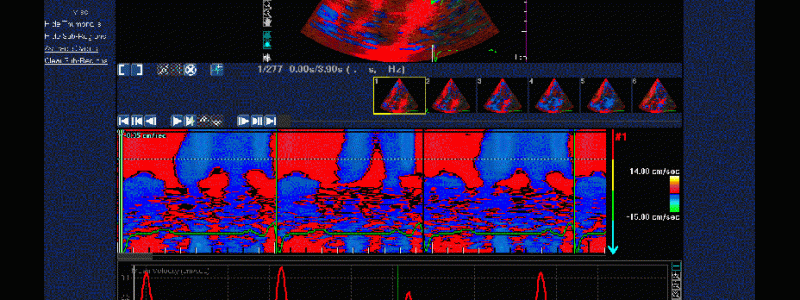

- Ich biete alle in der Praxis möglichen kardiologischen Untersuchungen und Möglichkeiten der Nachkontrolle inklusive implantierte elektronischer Geräte mit moderner Technologie an und arbeite mit allen kardiologischen Kliniken der Schweiz und dem Röngteninstitut IMAMED für weitergehende Untersuchungen zusammen. Ich investiere auch in technologische Fortschritte, die eine bessere oder weniger belastende Diagnostik erlauben. Aktuell habe ich das neueste Echokardiografiegerät von Philips als einer der Ersten in der Schweiz erworben (EPIC CVx). Ausserdem ist die Auswertung von Langzeit-EKG’s auf den neuesten Stand gebracht worden.